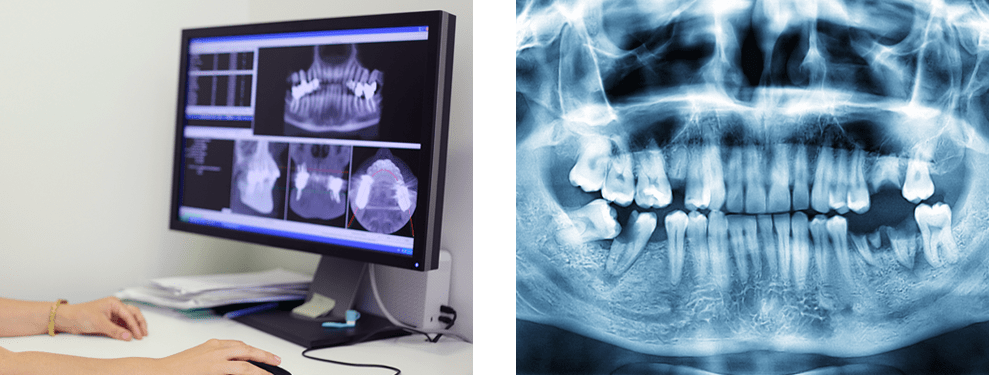

CTは水平・垂直・斜めと、見たい断面を自由自在に表示できるため、立体的(3次元)な画像診断が可能です。患者様の歯や骨の位置、距離などを確認し、インプラント材を埋入する際により精密・正確に検査を行い、モニターを見ながら口腔内の現状把握を行い、より安全な治療を可能にさせます。

インプラント治療や親知らずなどの外科手術では、インプラントを埋入する部分を正確な情報を知るために、CTを使用します。骨の高さや幅、神経の位置などを立体的に診査し、より正確で安全な治療を行います。CTを使うことで、顎の骨・関節・埋伏歯の診断、一般のレントゲンでは撮影できなかった部分を精緻に調べることができます。